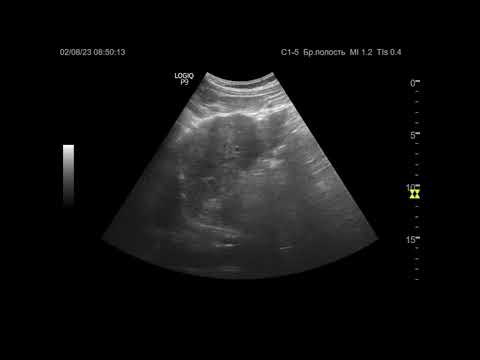

Ультразвуковая диагностика (УЗИ). Доктор Иогансен. Видеопримеры. Выпуск 54. Цирроз печени.

Эхосемиотика диффузных изменений печени. Часть 2. Цирроз печени и портальная гипертензия

Цирроз печени.Причины и методы диагностики